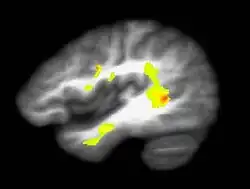

According to some reports, prolonged cannabis use (now termed CUD) causes decreased reactivity to dopamine, suggesting a possible link to an inhibited reward system and an increased addiction of severity.[16] Cannabis use disorder is now defined in the fifth revision of the Diagnostic and Statistical Manual of Mental Disorders, the main authoritative guide for mental health disorders in Australia.[10]